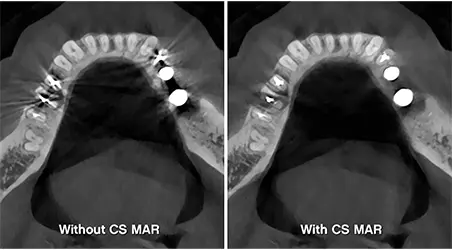

Enhanced Diagnostics

Capture detailed 3D images of teeth, bone, nerves, and soft tissue—seeing what traditional X-rays often miss. Perfect for identifying complex issues early.